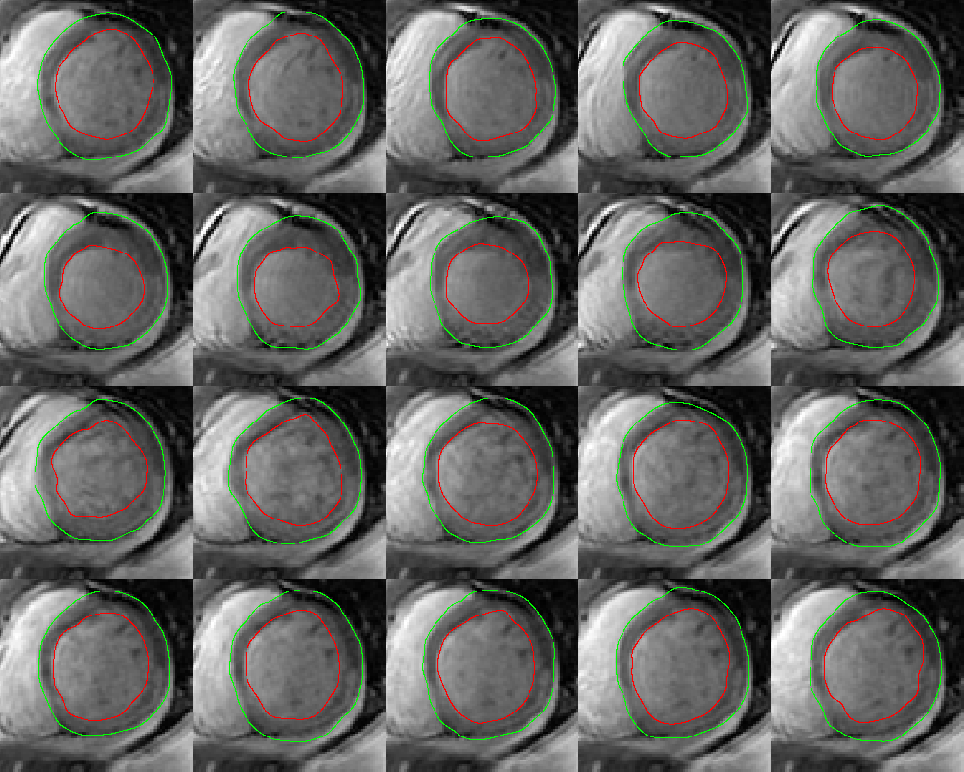

In this research the database provided by the authors of [23] is used. This database contains the MRI images of 33 patients which consists of 7980 two dimensional MRI images from different slices of the heart muscle. Each cardiac cycle is divided into 20 steps. These images are acquired from patients with different types of problems like Cardiomyopathy, Aortic regurgitation, Ischemia and Enlarged ventricles. All of patients were under 18 and the distance between slices is between 6 to 13 millimeters. Each image’s size is and the inner and outer contour of the heart is indicated by hand by the author of [23]. Based on the additional information attached to the database it is known that patient 23 suffers from Myocardial Infarction (MI). Also patients 18 and 25 have normal heart muscle which can be useful in understanding the effects of MI. Here the data from these three patients are used to achieve the results. Fig. 6 displays the cardiac cycle of the patient 23 for the first slice. The inner and outer contours of the left ventricle are determined in the images.